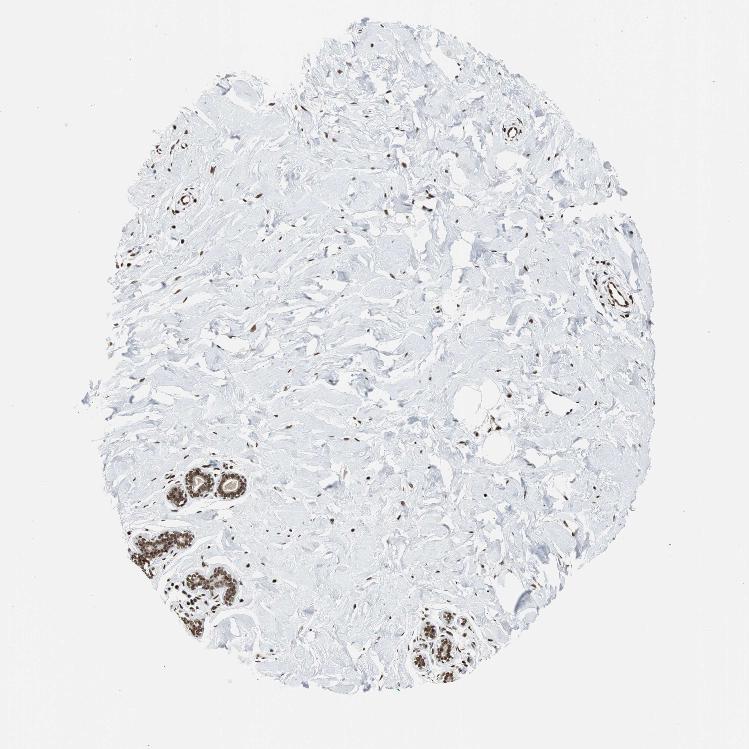

BREAST - Antibody stainingi

Antibody staining in the annotated cell types in the current human tissue is reported as not detected, low, medium, or high, based on conventional immunohistochemistry profiling in selected tissues. This score is based on the combination of the staining intensity and fraction of stained cells.

Each image is clickable and will lead to virtual microscopy that enables deeper exploration of all samples and also displays staining intensity scores, fraction scores and subcellular localization as well as patient and tissue information for each sample.

Antibody HPA006314Antibody HPA012010Antibody CAB011673

Adipocytes HighNot detectedNot detected

Glandular cells HighMediumMedium

Myoepithelial cells HighLowLow